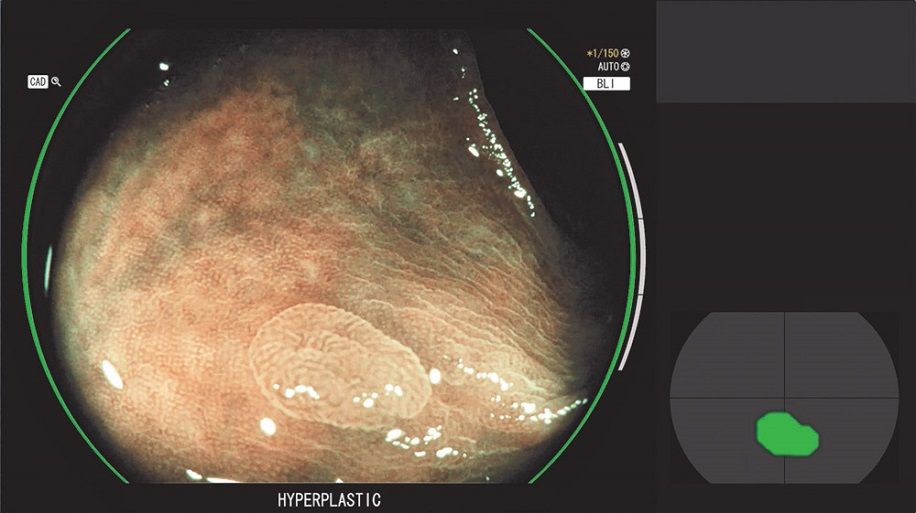

CAD EYE was developed to support real time detection of colonic polyps utilising AI technology. When a suspicious polyp is detected within the endoscopic image, a Detection Box indicates the area where the suspicious polyp has been detected accompanied by a sound signal. The new CAD EYE Characterisation will assist clinicians by generating a suggested histological prediction by displaying whether the suspicious polyp(s) in the image are hyperplastic or neoplastic.

CAD EYE Detection is activated when the clinicians are observing in White Light Mode or LCI Mode, and it automatically switches to CAD EYE Characterisation when the observation mode is changed to BLI Mode. CAD EYE can be activated or deactivated simply with just one click of the scope switch, which is also considered important when the functions are no longer necessary such as during therapeutic procedures.

The Graphical User Interface (GUI) was designed to minimise the endoscopists’ eye movements during a procedure, displaying the characterisation result and the Visual Assist Circle around the circumference of the endoscopy image. The Position Map is placed directly next to the side of the clinical image to show which area of the video image CAD EYE is focusing on.

CAD EYE Characterisation (Images below have been modified and shown for illustrative purposes only)